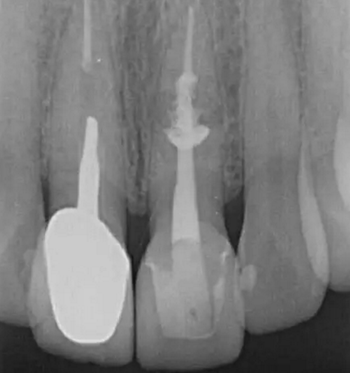

診斷:左上中切牙牙根內(nèi)吸收。治療計劃:左上中切牙根管治療,全冠修復(fù)。 治療過程:患者知情同意。使用含1/100,000腎上腺素的4%鹽酸阿替卡因(碧蘭麻,艾龍)局部浸潤麻醉,橡皮障隔濕。去腐未盡露髓,露髓孔出血多。開髓,使用10#不銹鋼K銼(MANI,日本)探查根管,根管中段有鈣化物阻擋,不能達到牙根全長(圖3A)。在顯微鏡下(Leica M400E,萊卡, 德國) 使用超聲尖(E1根管治療超聲尖,啄木鳥公司,中國)通開,采用根管長度測量儀(Root ZX, Morita公司,日本)加診斷絲片法(圖1B)測量根管長22 mm。使用控制扭矩馬達(X-smart,登士柏)和鎳鈦旋轉(zhuǎn)器械(Hero 642, Micromega)根管預(yù)備,根管預(yù)備過程中使用5.25%次氯酸鈉溶液沖洗。 根備完成后使用超聲蕩洗根管,5.25%次氯酸鈉溶液3 分鐘, 17% EDTA溶液1分鐘。干燥根管,使用螺旋充填器根管內(nèi)封氫氧化鈣糊,氧化鋅丁香油水門汀暫封。1周后患者復(fù)診,患者述無術(shù)后不適,檢查暫封完好,無叩痛,不松,牙齦無紅腫瘺管。使用橡皮障隔濕,去除暫封物,超聲蕩洗根管,5.25%次氯酸鈉溶液3 分鐘, 17% EDTA溶液1分鐘。干燥根管,牙膠尖(達雅鼎,中國)和必蘭根充糊劑(Cortisomol, 艾龍公司,法國)熱垂直加壓法根管充填。術(shù)后片顯示根充恰填,可見牙膠/糊劑被壓入鈣化物周圍和內(nèi)部縫隙內(nèi)

1月后復(fù)查無不適,行全瓷冠修復(fù)。8月2周后復(fù)查,患者無不適主訴,牙冠美觀,邊緣完好,患牙無叩痛,不松動,牙齦無紅腫瘺管, X線片示根周膜連續(xù),根尖周未見異常。建議患者避免用前牙撕咬食物,定期復(fù)查。 討論: 臨床上,由于牙根內(nèi)吸收和牙根外吸收的治療方法和預(yù)后不同,常需要對兩者進行鑒別診斷。過去通常采用偏移投照的方法鑒別兩者。在偏移投照片上,外吸收病損和根管輪廓相對位置較正位片會發(fā)生變化,而內(nèi)吸收病損則不會[12]。